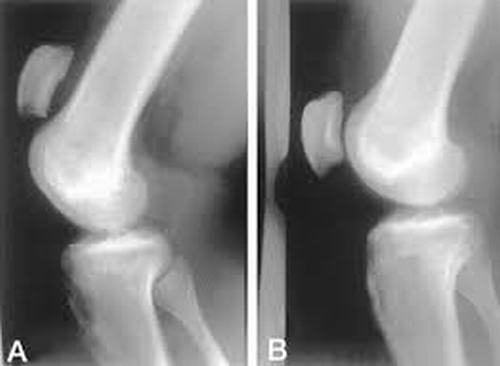

Nguyên nhân gây thoái hóa xương bánh chè

Thoái hóa xương bánh chè hay còn được gọi là thoái hóa xương đầu gối, bệnh phổ biến ở người cao tuổi nhưng đang có xu hướng trẻ hóa. Vậy nguyên nhân gây thoái hóa xương bánh chè? Cách điều trị bệnh như thế nào?

Thoái hóa xương bánh chè hay còn được gọi là thoái hóa xương đầu gối